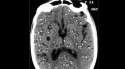

You usually wont notice you have it until one or twenty of the juveniles lodge in your brain and you start having seizures